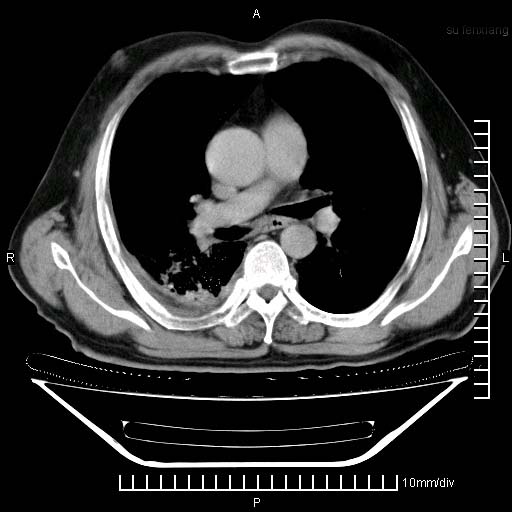

标题: CT24043:胸部增强:男性,60岁

既往肺结核,近10几天,咳嗽,咳痰,右侧胸痛,疼痛较明显,右上肺斑块考虑结核灶胸膜粘连,增强,可惜动脉期没有定好,未见强化,可延迟4分后又见较明显强化,中心见低密度影,如果说结核是边缘强化,可这个灶强化的面积挺大的,让人很挠头。

动脉期